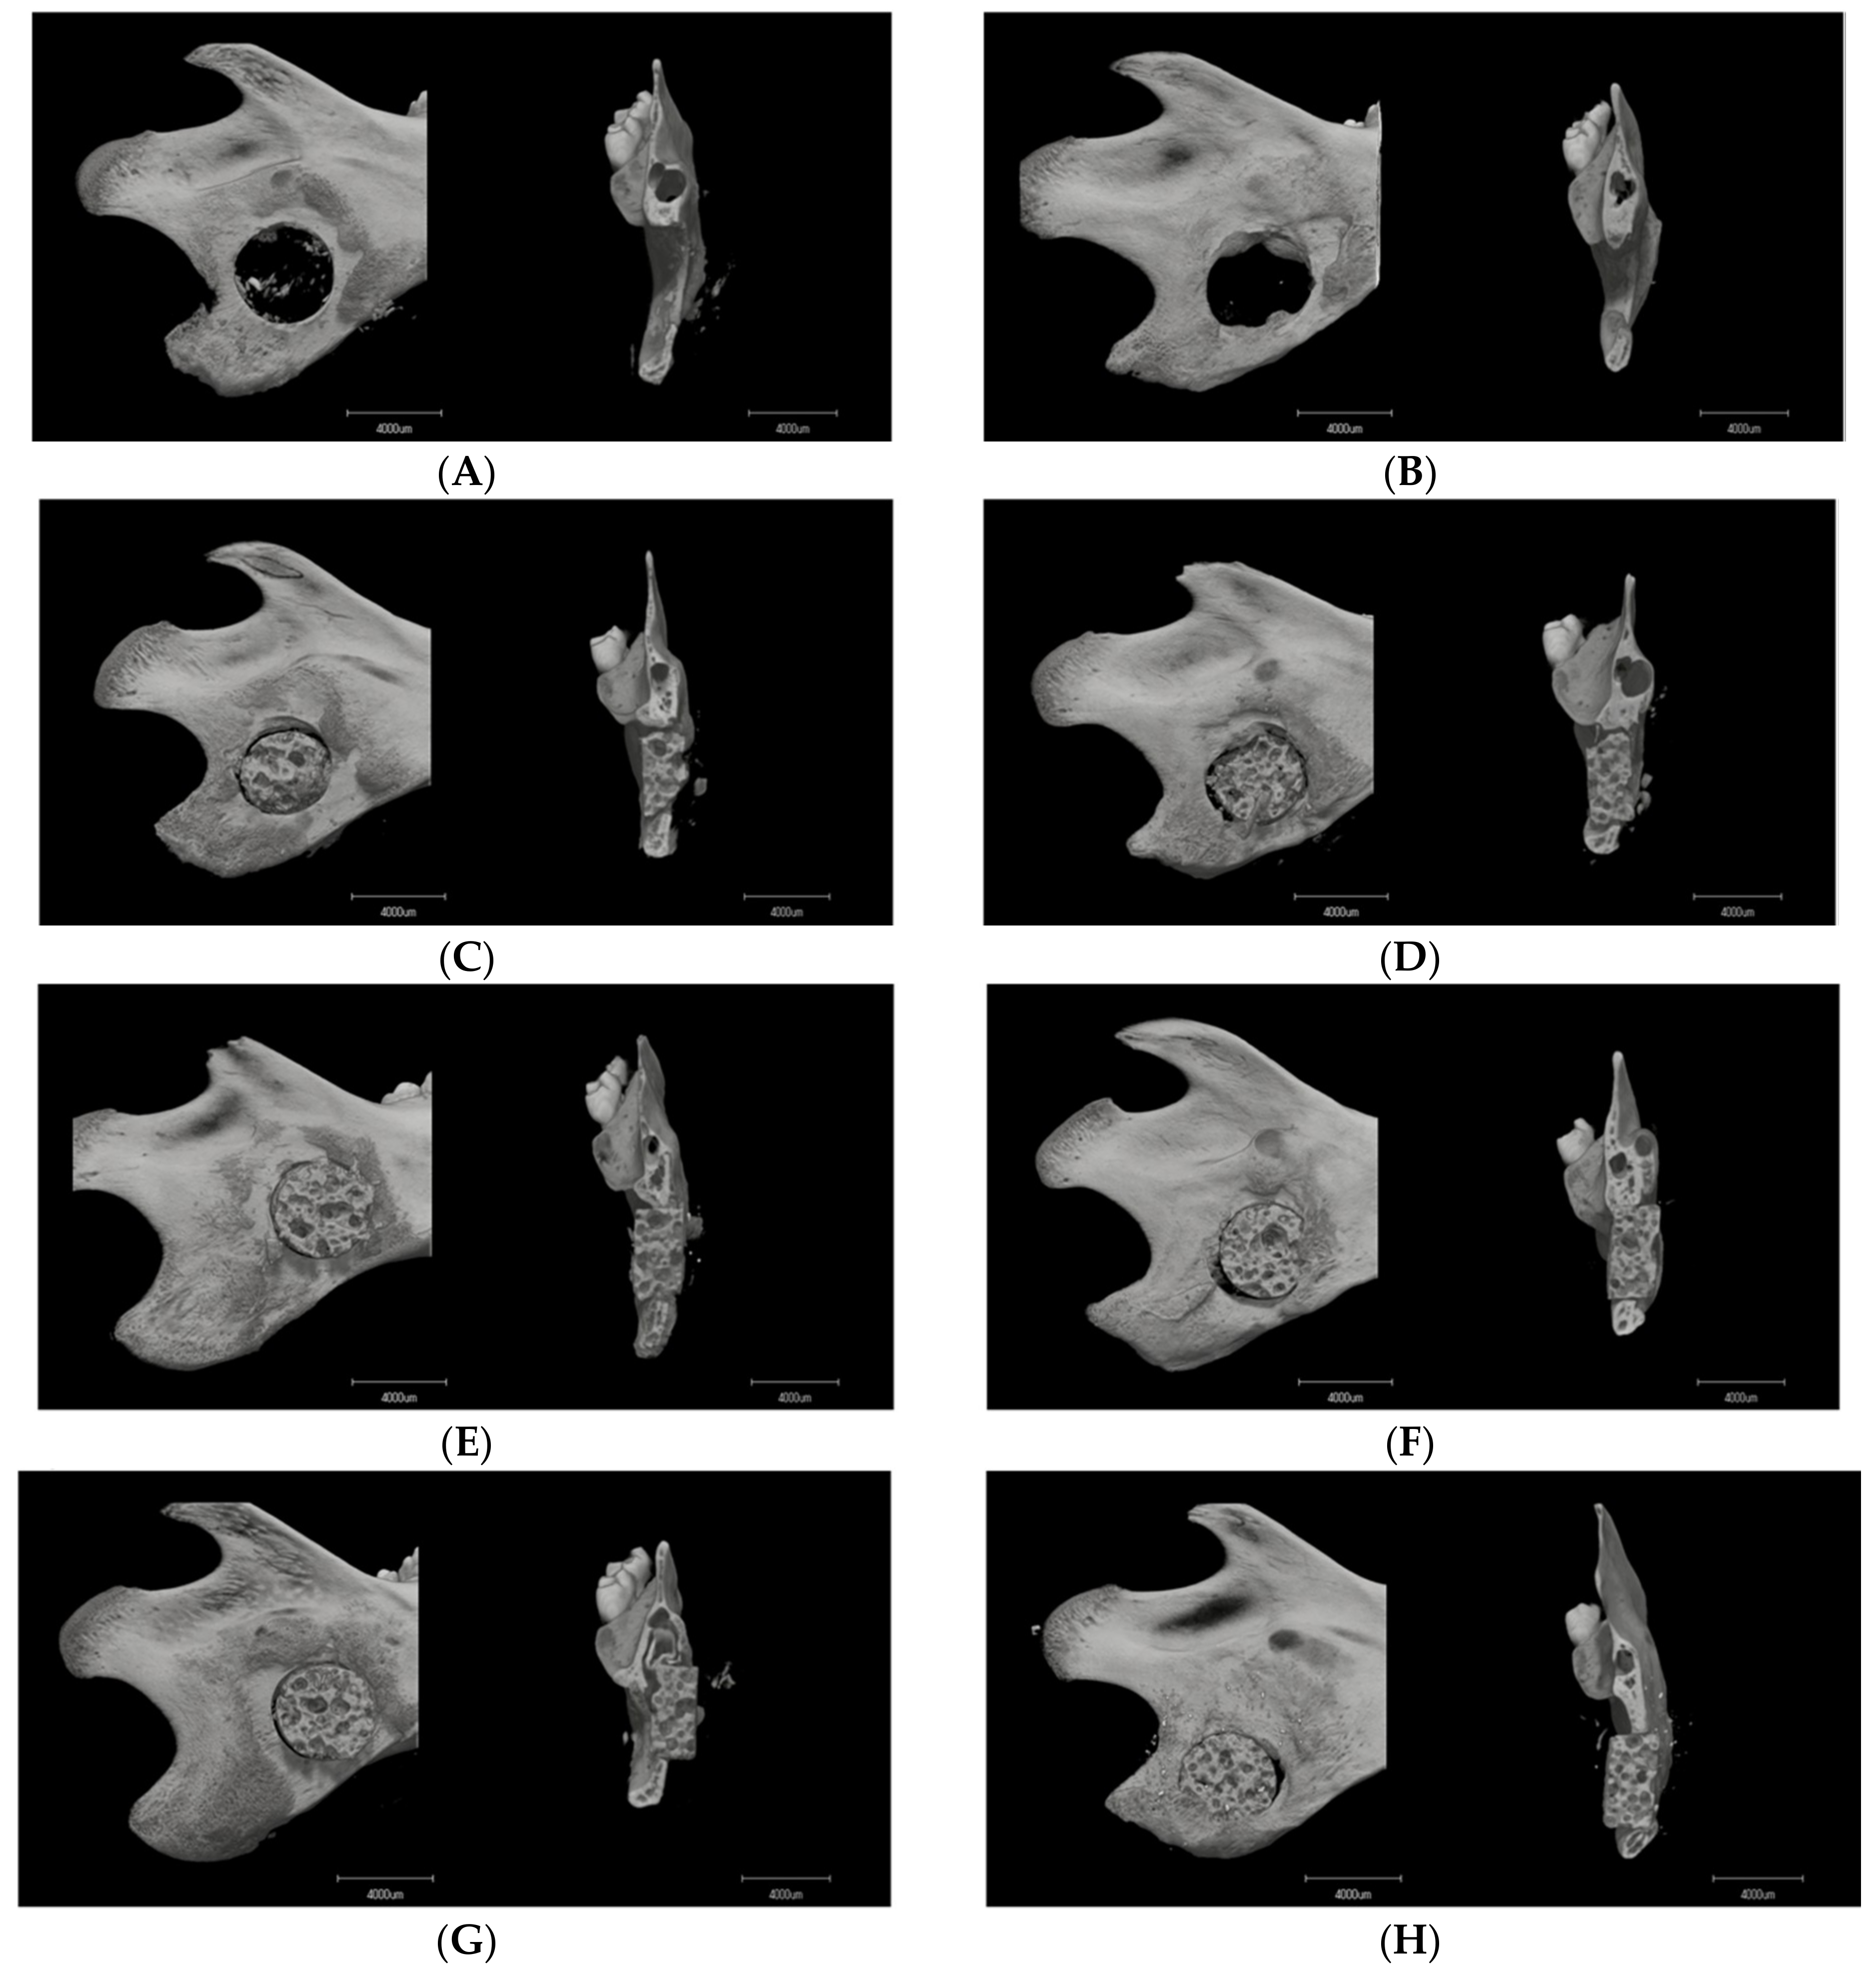

3.1. Micro-CT Analysis

3.1.1. Image Description

3.1.2. Material–Host Bone Combinations and the Quantity of Newly Formed Osteoid Tissue

3.1.3. Difference in Osteogenesis between the Superior and Inferior Sides of the Critical Mandibular Defect